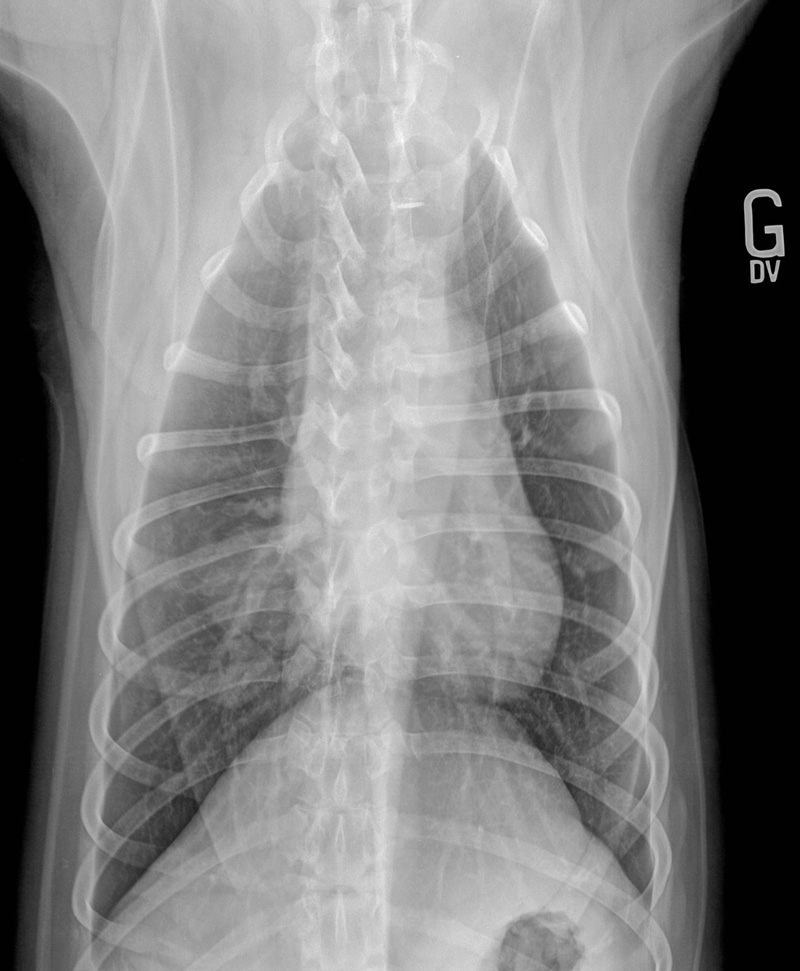

Voici deux clichés radiographiques obtenus d’un Bouvier bernois de 6 ans présenté pour des signes neurologiques suggérant une atteinte du thalamocortex.